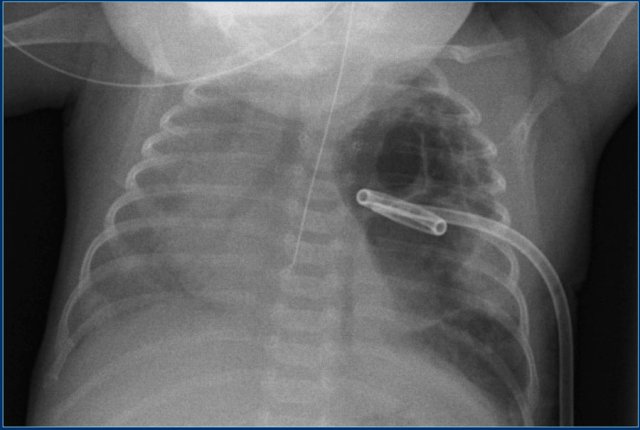

Chest drainage tube

Chest drainage tube are placed in case of respiratory distress caused by pleural fluid or pneumothorax in order to allow sufficient expansion of the lung for ventilation.

The tube should be positioned in the midaxillary line via the 4th - 6th intercostal space.

The position should be apical anterior in patients with a pneumothorax.

Study the image.

Then continue reading.

The findings are:

1. Endotracheal tube in good position.

2. Straight chest drain tube in good position. Drainage however is not optimal.

3. Mediastinal shift to the right. There is however no tension-pneumothorax, since the diaphragm has a normal convex upper border.

In this patient, who has a large pneumatocele, a pigtail catheter is placed in the pneumatocele.